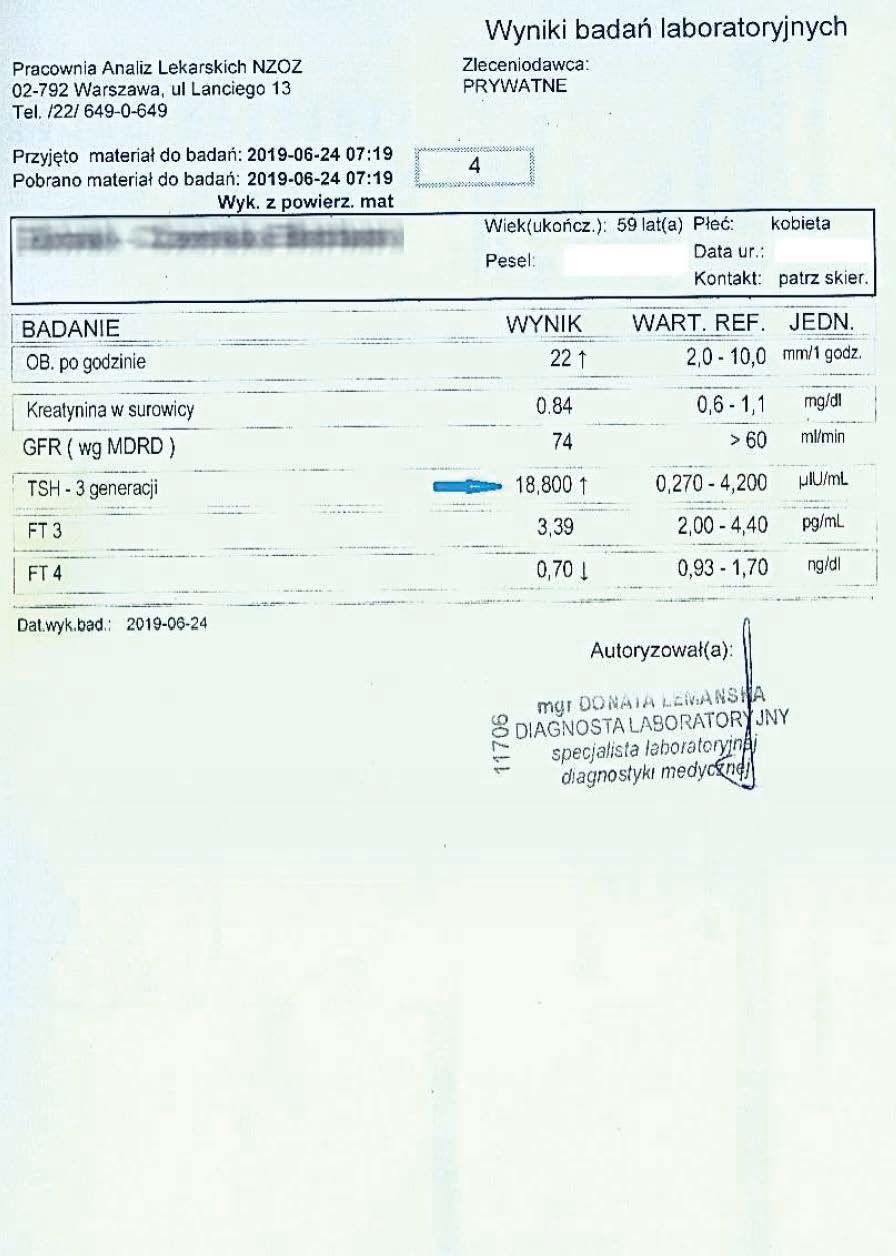

PRZYKŁAD EFEKTU PREPARATU NA NIEDOCZYNNOŚĆ TARCZYCY

Kobieta lat 59 z niedoczynnoscią tarczycy, bez przyjmowania lewotyroksyny. Kobieta przyjmowała preparat przez okres ponad 3 miesięcy. Przy zachowaniu naturalnego cyklu komórkowego i stałemu stymulowaniu mitochondriów osiągneła następujące wyniki kuracji:

Po zaobserwowaniu znacznej poprawy w ogólnym samopoczuciu, kobieta postanowiła wykonywać badania ze zwiększoną częstotliwością oraz kontrolę prób wątrobowych.

Po kolejnych dwóch miesiącach kobieta ponownie wykonała badania. Widoczne są: spadek TSH, obniżenie stanu zapalnego jak i spadek markeru wątrobowego GGTP.

Sukcesywnie co 2 miesiące można zaobserwować stały spadek parametrów zarówno wątroby jak i tarczycy. Kolejne badania potwierdzały dalszy spadek parametrów.

Po ponad roku kuracji badania wykazały dalszy postęp wycofania autoimmunologi tarczycy, potwierdzone również badaniem USG narządu.

Preparat wpływając na odbudowę mitochondriów zapewnił podłoże energetyczne do produkcji hormonów i odbudowy narządu. Brak ingerencji farmakologicznej wykazuje skuteczność nawet w podeszłym wieku, gdzie regeneracja jest wolniejsza a reakcje anaboliczne w znacznym stopniu spowolnione. Można zaobserwować także działanie ogólnoustrojowe obserwując spadek markeru wątroby, co jasno wykazuje poprawę funkcjonowania całego organizmu.